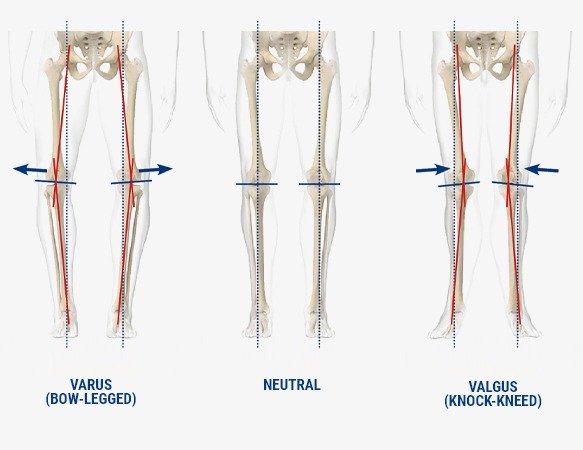

Mechanical alignment: A “one-size-fits-all” approach

Mechanical alignment is the traditional technique used in knee replacement surgery. It positions the implants to form a straight line from the hip to the knee and down to the ankle, often called a neutral mechanical axis. Although this approach can create a symmetrical leg shape, it does not always reflect a person’s natural anatomy or the way their knee previously moved.

Kinematic alignment aims to restore the natural alignment and joint motion that were unique to your knee before arthritis developed. Instead of creating the same straight alignment for every patient, this technique works with your individual anatomy by respecting your original joint lines, ligament balance, and bone shape.